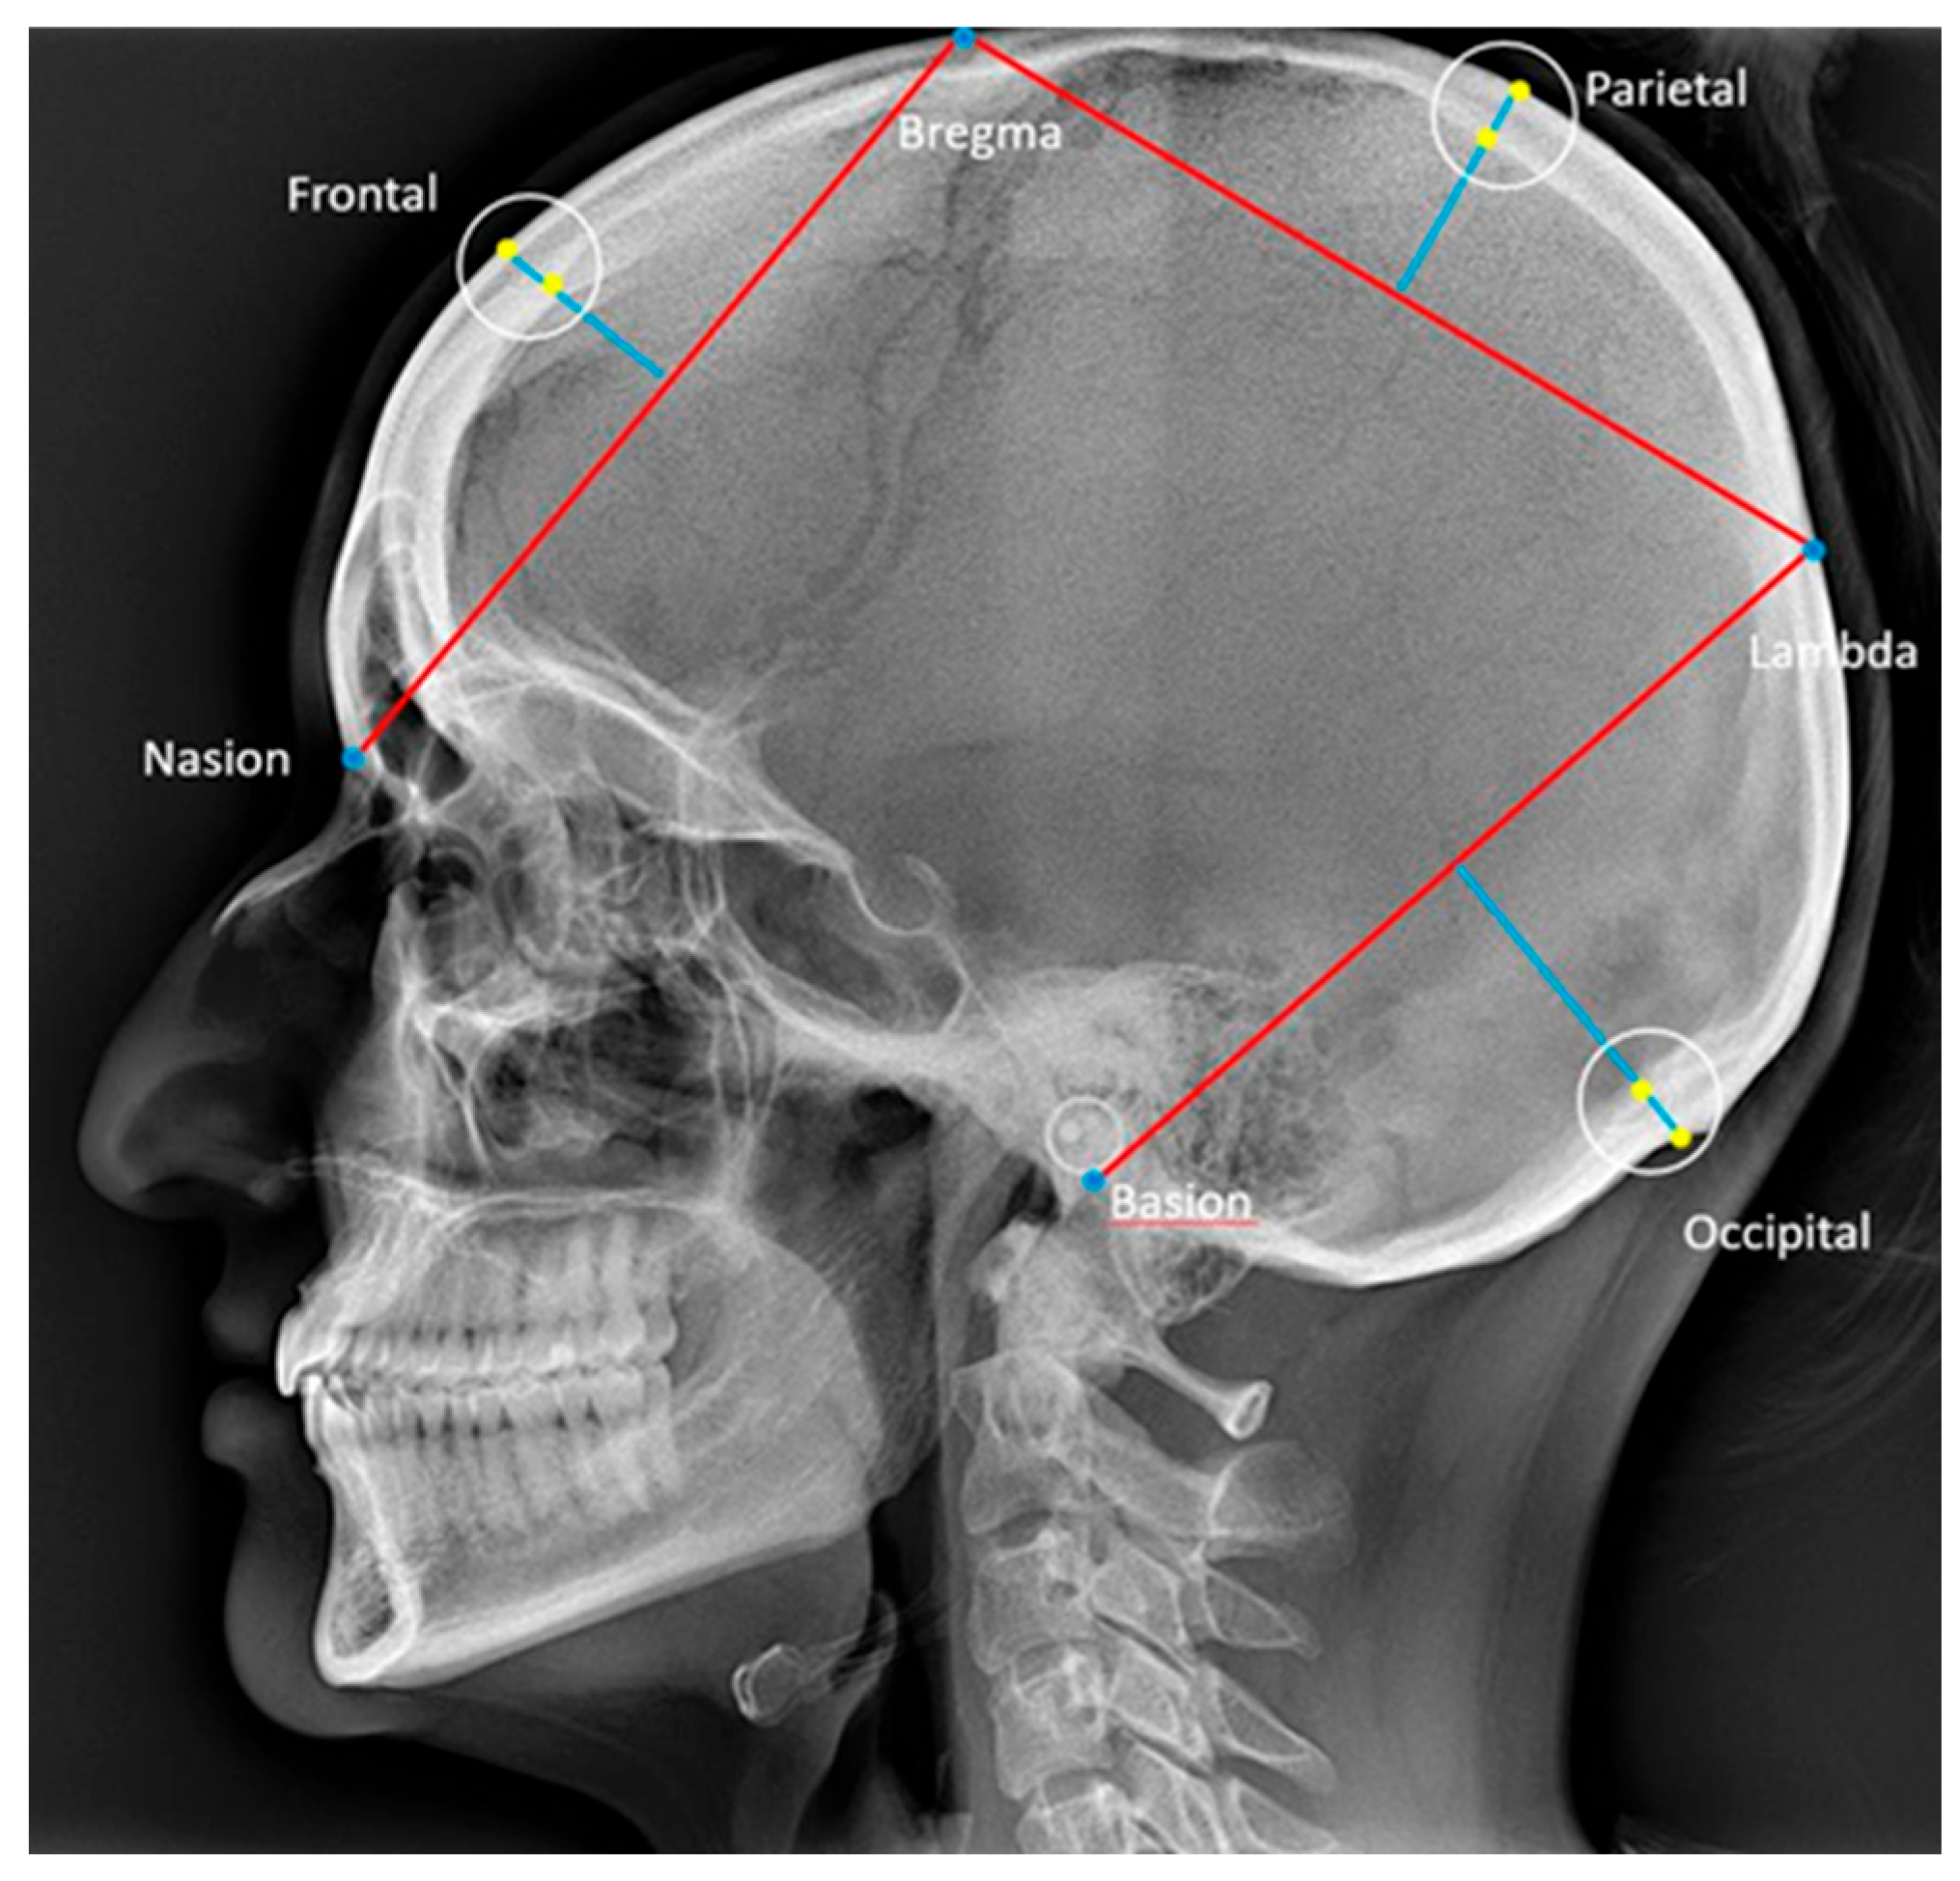

2.2.1. Cephalometric Analysis of Lateral Cephalograms

| Variable | OSA | Control | Comparison | ||||||||

| Skull thickness (mm) | |||||||||||

| Frontal | 50 | 3.5 | 11.4 | 6.73 | 1.57 | 72 | 4.0 | 11.2 | 6.61 | 1.45 | 0.733 |

| Parietal | 48 | 4.4 | 11.5 | 7.83 | 1.55 | 71 | 4.8 | 11.9 | 7.35 | 1.54 | 0.839 |

| Occipital | 49 | 2.9 | 14.4 | 7.3 | 2.59 | 74 | 3.4 | 11.8 | 6.78 | 1.99 | 0.991 |

| Nasal bone length (mm) | |||||||||||

| Nasal bone length | 50 | 12.2 | 31.1 | 21.4 | 4.25 | 74 | 16.5 | 27.9 | 21.68 | 3.27 | 0.794 |